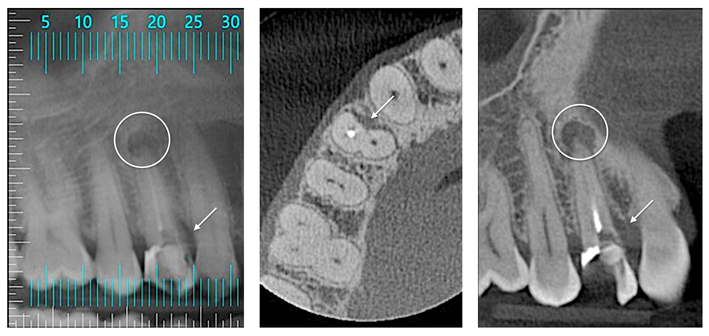

Paciente jovem (32 anos) apresentou-se na clínica com o primeiro pré-molar superior direito com fratura corono-radicular e grande lesão periapical com rompimento da cortical vestibular, sendo, portanto, indicada a extração dentária. Dada a idade do paciente e a importância de se manter a estética e a função na região, optou-se pela instalação imediata de implante dentário associada à preservação e regeneração alveolar.

Após o diagnóstico e planejamento, baseados em exames radiográficos e clínicos (Figuras 1 e 2), a primeira etapa foi realizar uma extração dentária atraumática (secção dentária e utilização de periótomo fino e flexível), visando a preservação completa do periodonto de sustentação. Após a curetagem para remoção total da lesão periapical, fez-se a instalação do implante alcançando-se um ótimo travamento inicial e um correto posicionamento ápico/coronal e tridimensional (Figura 3). O Túnel Check, da Implacil De Bortoli (Figura 4), foi utilizado para avaliar o posicionamento tridimensional do implante e selecionar a altura correta do cicatrizador – optou-se por um cicatrizador ao invés do parafuso de cobertura do implante para que não houvesse formação óssea sobre o parafuso, o que tornaria a reabertura muito mais traumática. Após, a membrana Cytoplast TXT 200 Singles (Implacil De Bortoli) foi personalizada e instalada inicialmente na face palatina (Figura 5 – ela não deve ficar tocando nas faces proximais dos dentes vizinhos), seguido do preenchimento alveolar (Figura 6) com substituto ósseo natural contendo 25% de colágeno, o Extra Graft XG-13 (Implacil De Bortoli). Por conter colágeno na sua composição, o Extra Graft XG-13 não fica liberando as partículas ósseas ao longo do processo de osteointegração.